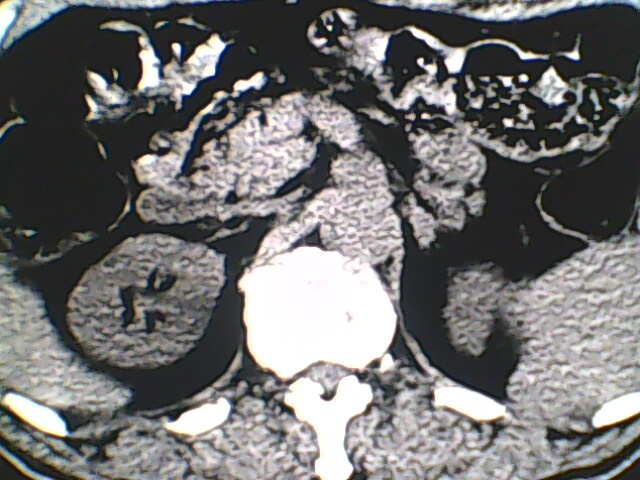

男,56岁,高血压,临床怀疑肾上腺问题,肝脏怎么那么高啊?能描述一下么?

右侧膈膨升,间位结肠,胸腰椎退行性骨关节病,右侧肾上腺可疑增生(图像颗粒太粗,窗太窄,不好看)。

支持 右侧膈膨升,间位结肠;胸腰椎退行性骨关节病;双侧肾上腺可疑增生。